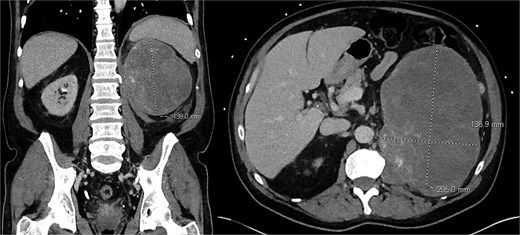

Computed tomography (CT) abdomen/pelvis demonstrated a 20.5 × 13.7 × 13.9 cm hypoenhancing lobulated mass in the left upper quadrant with stippled areas of calcification within the mass (Fig. 1). There was a maintained fat plane between the mass and kidney. The left adrenal gland was not definitely visualized. Given the radiologic findings, the presumptive diagnosis of an ACC was made. There was no evidence of metastatic disease or local invasion into the renal vein or vena cava. A normally enhancing right kidney was seen.

Pre-operative CT scan of abdomen/pelvis findings of a left upper quadrant abdominal mass.